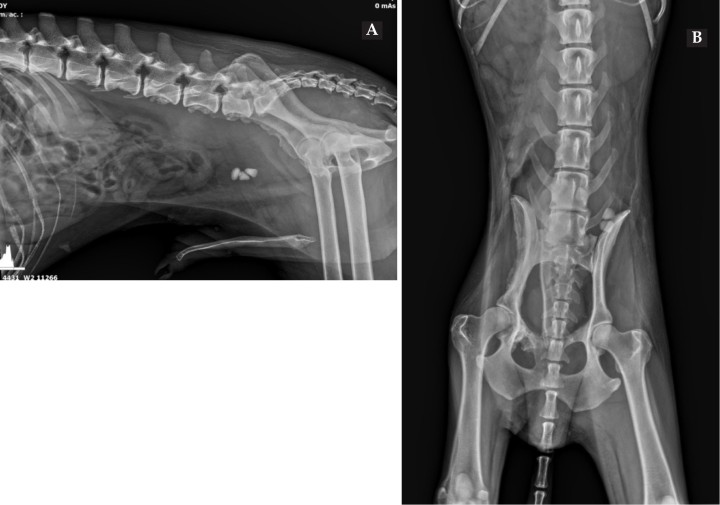

A nivel de las estructuras óseas, se aprecian reacciones periósticas irregulares con bordes bien definidos en los márgenes ventrales de los cuerpos vertebrales de L5, L6 y L7, así como en las superficies ventral y lateral del ilion derecho y en la rama craneal del pubis derecho (Fig. 2). Dichas neoformaciones no provocan discontinuidad de las superficies óseas.

<p>Mismas imágenes que la Figura 1. En ambas proyecciones (<strong>A</strong> y <strong>B</strong>) se observan 3 urolitos en vejiga de la orina (flecha verde), prostatomegalia (línea roja) y lesiones osteoproliferativas en el borde ventral de los cuerpo vertebrales de L5-L6-L7, ilion y pubis (flechas amarillas). En proyección lateral derecha (<strong>A</strong>) se aprecia un aumento focal del tamaño y opacidad del retroperitoneo ventralmente a L6-L7 (flechas azules).</p>

Mismas imágenes que la Figura 1. En ambas proyecciones (A y B) se observan 3 urolitos en vejiga de la orina (flecha verde), prostatomegalia (línea roja) y lesiones osteoproliferativas en el borde ventral de los cuerpo vertebrales de L5-L6-L7, ilion y pubis (flechas amarillas). En proyección lateral derecha (A) se aprecia un aumento focal del tamaño y opacidad del retroperitoneo ventralmente a L6-L7 (flechas azules).

Ventralmente a los cuerpos vertebrales de L6 y L7 se visualiza un aumento focal de tamaño del espacio retroperitoneal con opacidad tejido blando que provoca desplazamiento ventral del colon descendente.

La vejiga de la orina, parcialmente distendida, presenta 3 estructuras redondeadas y de opacidad mineral. Caudalmente a la misma, se visualiza la silueta de la próstata aumentada de tamaño, excediendo el 70 % de la distancia entre el promontorio del sacro y el pubis.